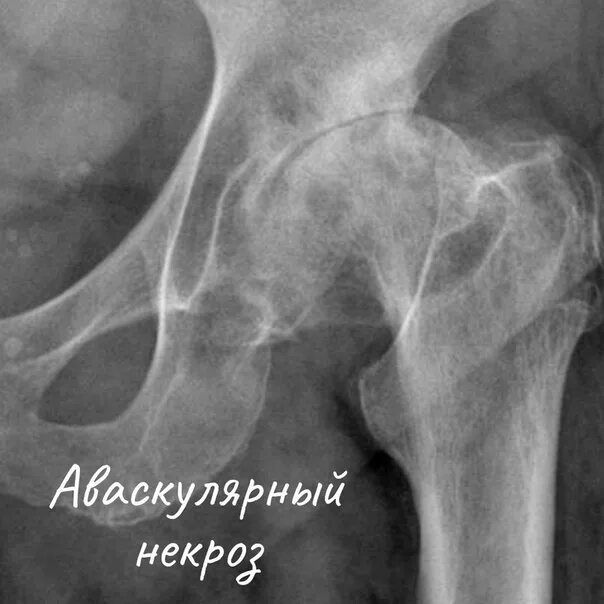

Боли при некрозе тазобедренных суставов